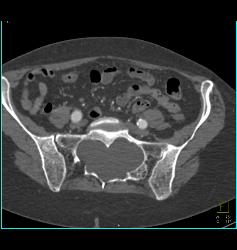

GSW With Fracture and Spasm in Brachial Artery